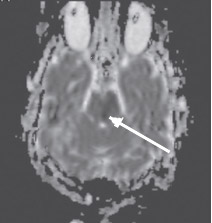

Неинформативность методики ДВИ в определении острого ишемического поражения при локализации в стволе головного мозга можно объяснить двумя факторами. Во-первых, наличием малых ишемических очагов, поскольку перфорирующие артерии васкуляризируют очень маленькие зоны ствола головного мозга. По-видимому, большая часть ложноотрицательных результатов у пациентов с инфарктом ствола головного мозга и незначительным или обратимым неврологическим дефицитом была обусловлена наличием ишемического очага ниже пространственного разрешения изображения (Oppenheim C. et al., 2000; Toi Н. et al., 2003). Во-вторых, нейроны ствола головного мозга (образования более старого в филогенетическом отношении) более стойкие к ишемии, чем нейроны более молодых эволюционно полушарий большого мозга. Это могло быть одной из причин более высокой толерантности их к ишемии и более позднего развития цитотоксического отека ткани ствола головного мозга (Oppenheim C. et al., 2000; Rovira A. et al., 2002; Toi H. et al., 2003). Как известно, ДВИ отображают наличие цитотоксического отека в ишемических очагах ярким сигналом (рис. 4), который соответствует темному сигналу на карте диффузии (рис. 5), обусловленному низким ИКД.

Рис. 5. Острый инфаркт моста головного мозга. Карта диффузии (аксиальная проекция). Гипоинтенсивный (темный) МР-сигнал в левой

половине моста соответствует низкому ИКД, обусловленному цитотоксическим отеком